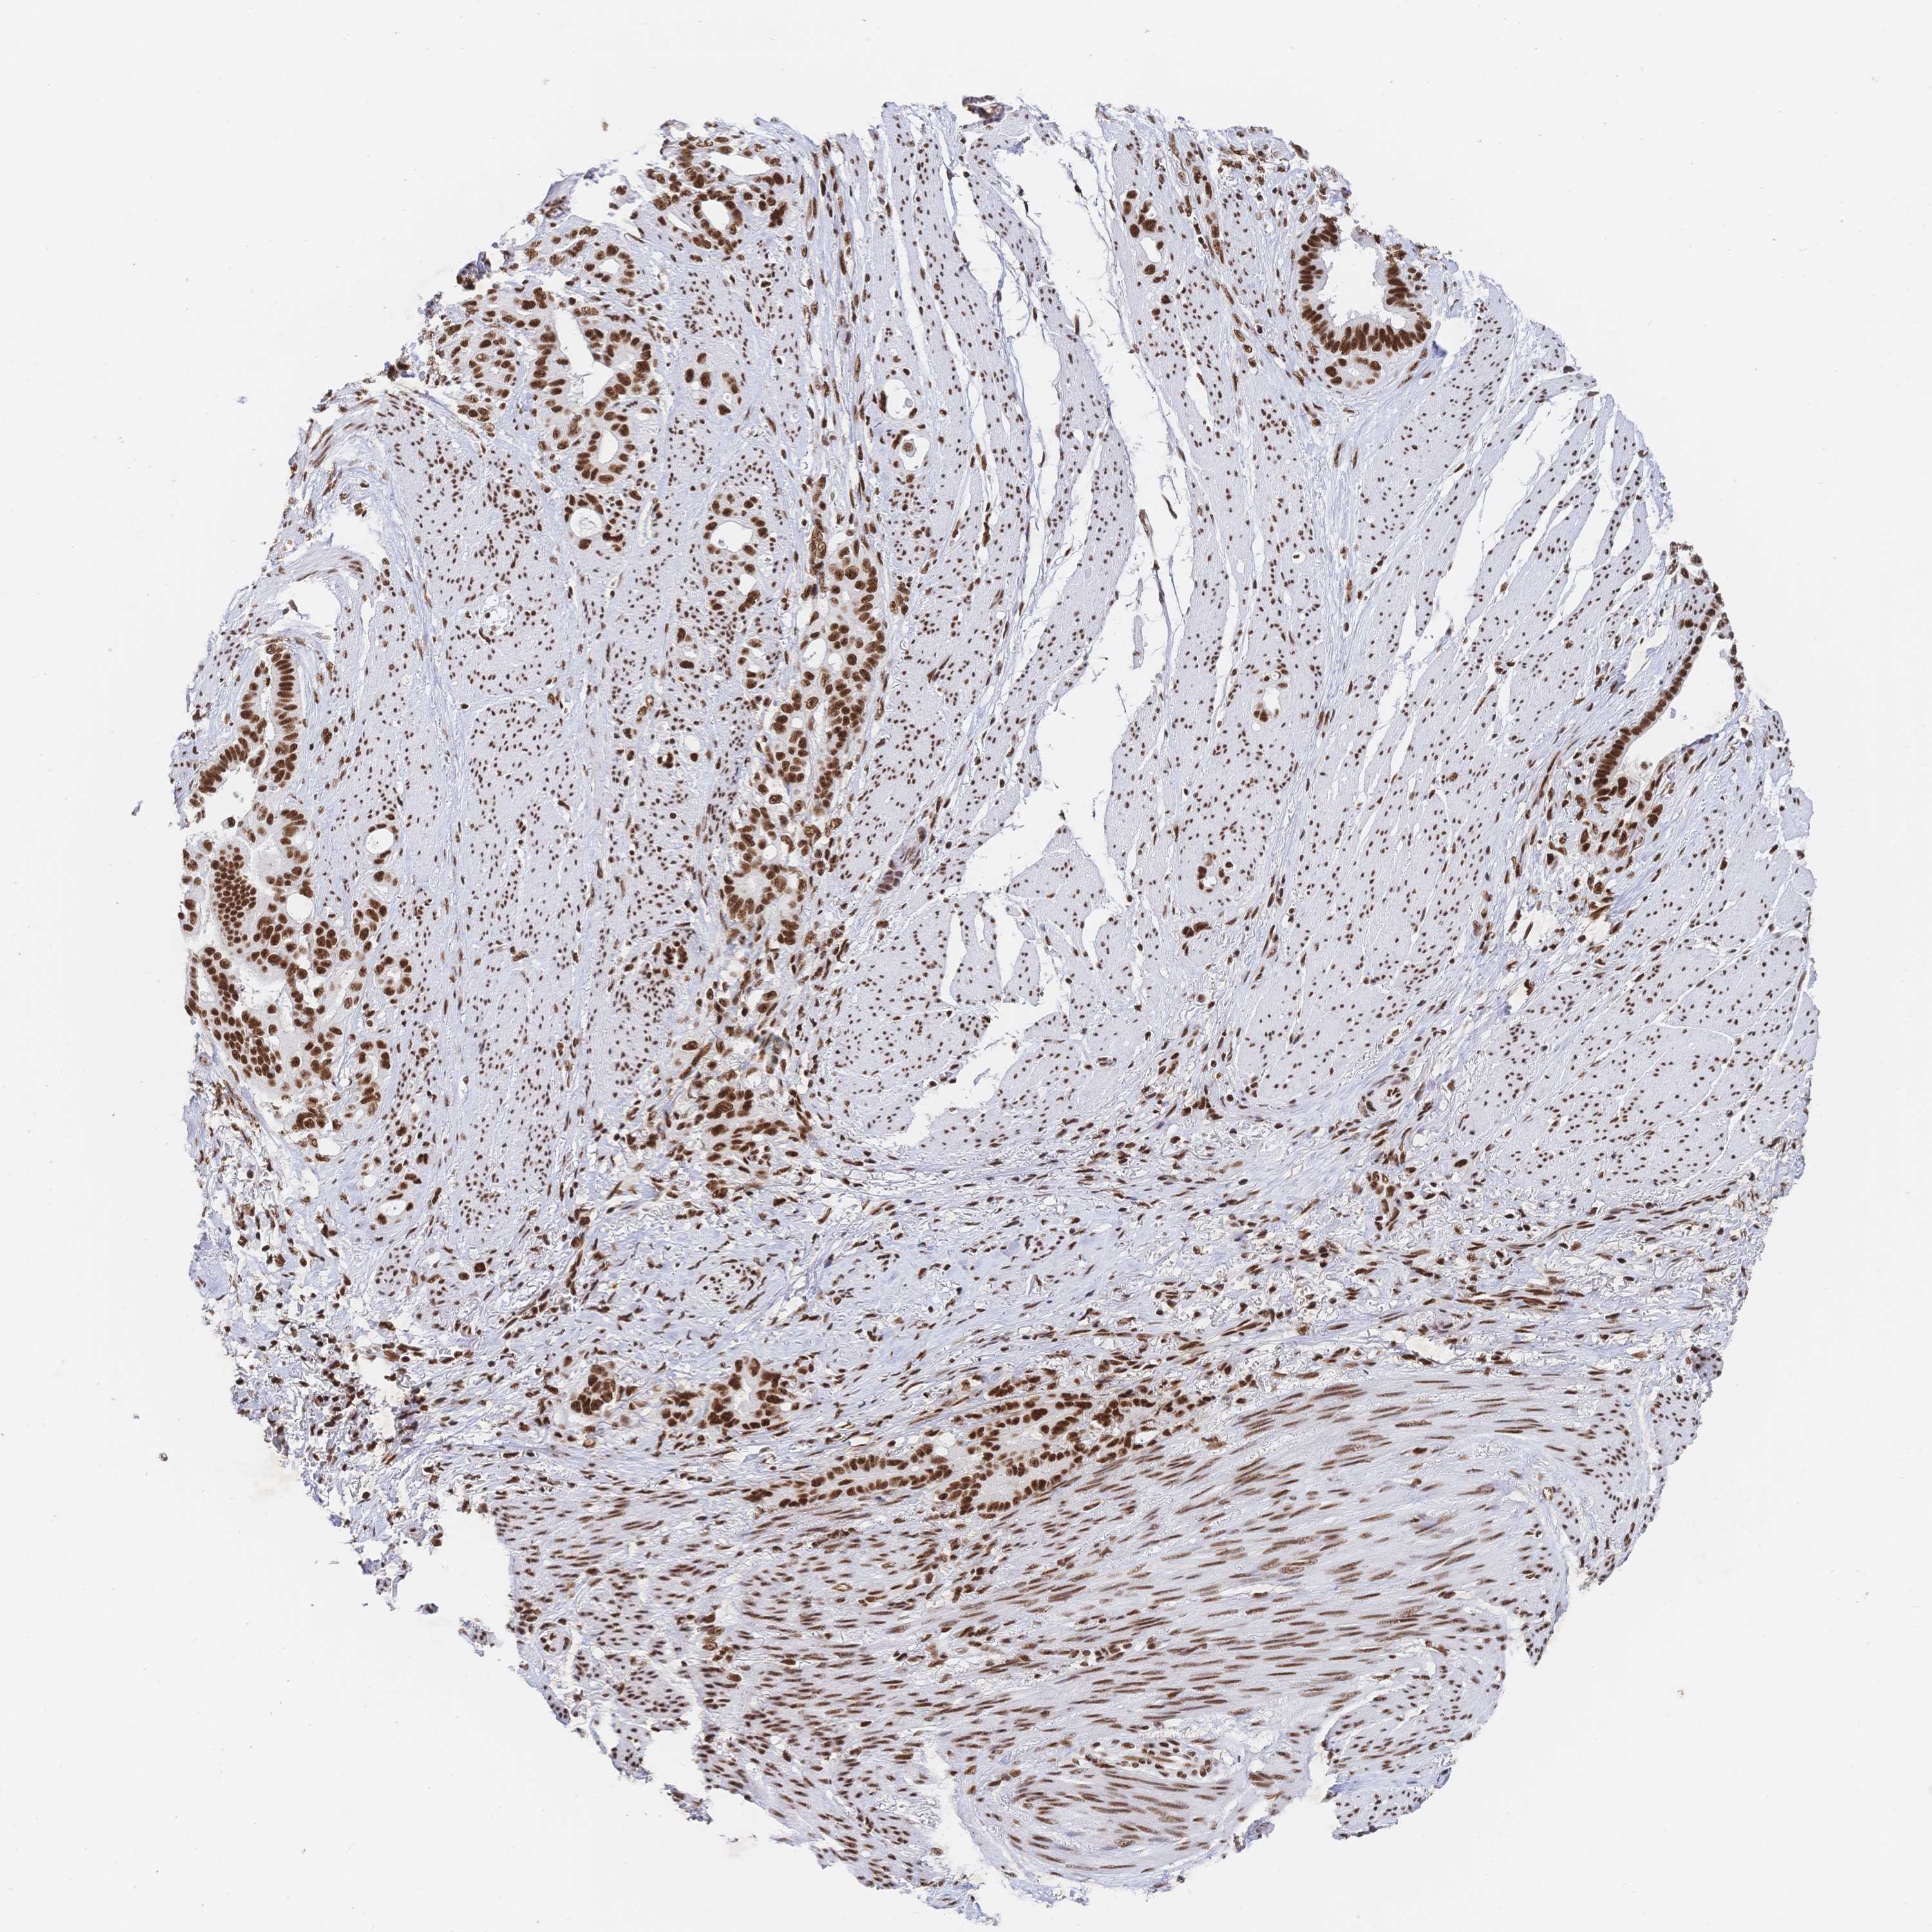

STOMACH CANCER - Protein expressioni

A mouse-over function shows sample information and annotation data. Click on an image to view it in a full screen mode. Samples can be filtered based on level of antibody staining by selecting one or several of the following categories: high, medium, low and not detected. The assay and annotation is described here.

Note that samples used for immunohistochemistry by the Human Protein Atlas do not correspond to samples in the TCGA dataset.

Antibody stainingi

Antibody staining in the annotated cell types in the current human tissue is reported as not detected, low, medium, or high, based on conventional immunohistochemistry profiling in selected tissues. This score is based on the combination of the staining intensity and fraction of stained cells.

Each image is clickable and will lead to virtual microscopy that enables deeper exploration of all samples and also displays staining intensity scores, fraction scores and subcellular localization as well as patient and tissue information for each sample.

Antibody HPA061301

Antibody CAB013073

Staining

High

Medium

Low

Not detected

Intensity

Strong

Moderate

Weak

Negative

Quantity

>75%

75%-25%

<25%

None

Location

Nuclear

Cytoplasmic/membranous

Cytoplasmic/membranous,nuclear

Adenocarcinoma, NOS

Adenocarcinoma, High grade